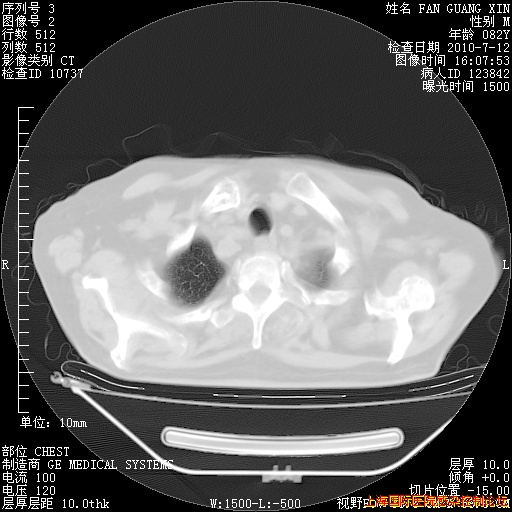

今天复查CT

今天CT

整整相隔30天的肺部CT好像有所好转啊。甲强龙减量第3天,需要观察体温。